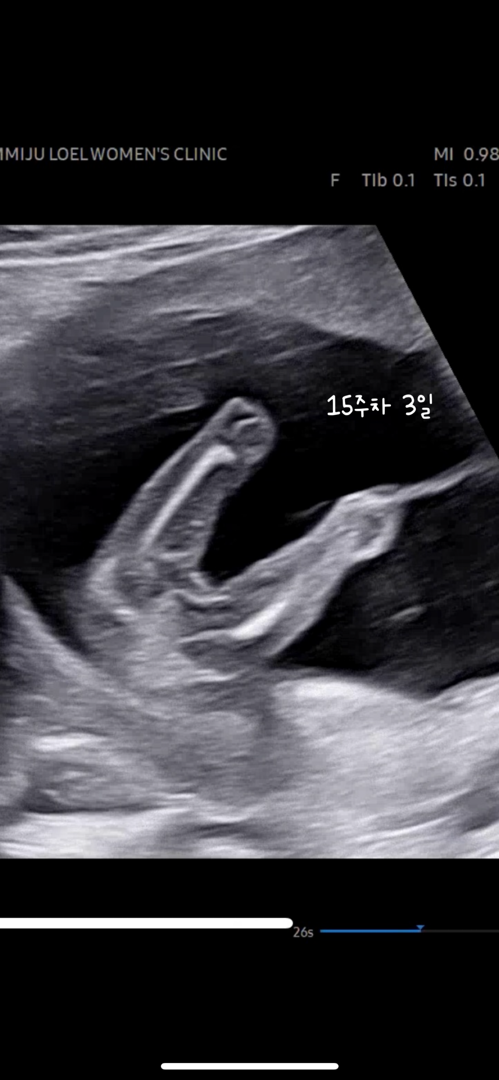

15주차, 16주차 초음파 아이 성별

15주차 3일 초음파는 딸인 것 같고, 16주차 초음파는 아들처럼 보여요 친구들과 젠더리빌 파티를 하기로 해서 아직 성별을 모르는 상태인데, 너무 궁금해서 여쭤봅니다! 어떤 성별로 보이실까요?🥹 댓글에 16쥬차 초음파도 있어요!

딸같아요! 밑에 사진은 탯줄같아요 아들이면 완전 뾰쪽이예요!

봐주셔서 감사해요! 성별은 딸이었어요ㅎㅎㅎ 오늘도 행복한 하루 보내세요🩵